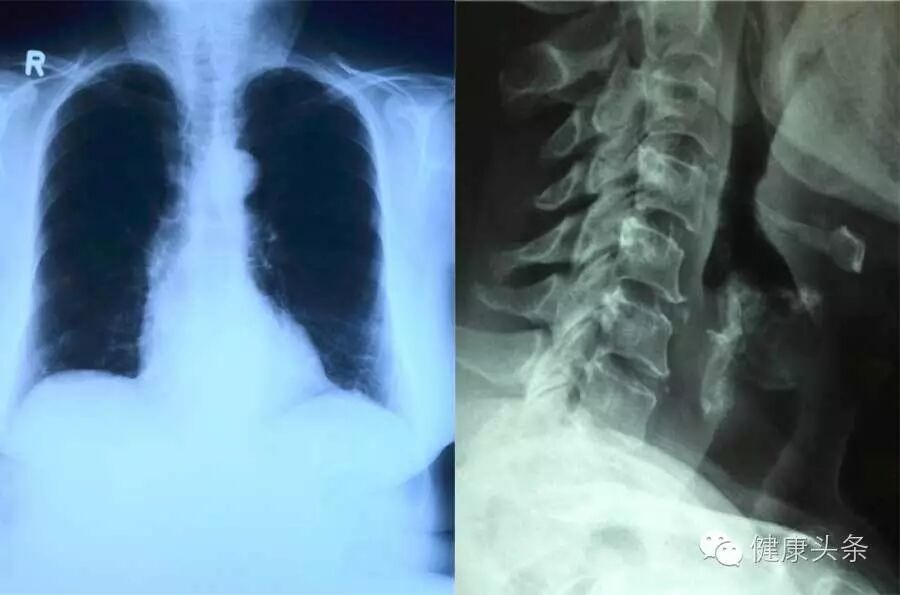

俗称「拍片」。体检时常说的胸片,就是它啦。

而常规体检中的胸片,则能够粗略检查心脏、主动脉、肺、胸膜、肋骨等。可以见到如心影增大、肺纹理增多、肺部钙化点、主动脉结钙化等,帮助判断心血管疾病的风险以及病情严重程度。

另外,脊柱侧弯、颈椎屈曲等问题,也可以用 X 线片来初步判断。

由于是人体组织的平面重叠图像,所以诊断具有一定的局限性。但因为 X 线片检查快速、价格低廉,故常被用于体检,用来筛查某些病症。